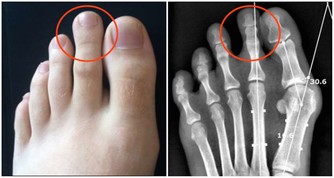

(圖片來源:資料圖庫)